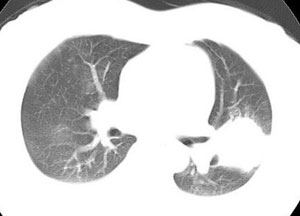

女性,30岁。

病史为胸痛20多天,无畏寒发热,无消瘦,无咳嗽咳痰。总之症状很逍遥。

临床以胸痛待查收住入院。

双肺野可见散在大小不等结节及肿块影,内密度不均匀,边缘部分清,部分欠清,纵隔未见明显肿大淋巴结.右侧胸腔少理积液.结合临床,考虑韦格肉芽肿可能吧,巨淋巴增生,结节病,特殊感染都要考虑.转移瘤临床不象.

本病例特点如下:

1.青年女性,以胸痛20多天就诊,无呼吸道及感染临床症状体征,无原发肿瘤病史;

2.肺ct表现为两肺多发大小不等结节影,大结节位于肺尖部,小结节多位于肺外带胸膜下,大结节内可见支气管充气征,周围可见月晕征(指在结节状或肉芽肿样病灶周围呈环形磨玻璃影),右肺门及腔静脉后可见小淋巴结,右侧胸腔内少量液体。

两肺散在分布大小不等的肿块及结节影,边缘毛糙,有分叶、毛刺,病灶密度不均匀,可见支气管充气相与空泡征。病变大多位于胸膜下,可见胸膜凹陷及胸腔积液。气管腔静脉间可见小结节影。